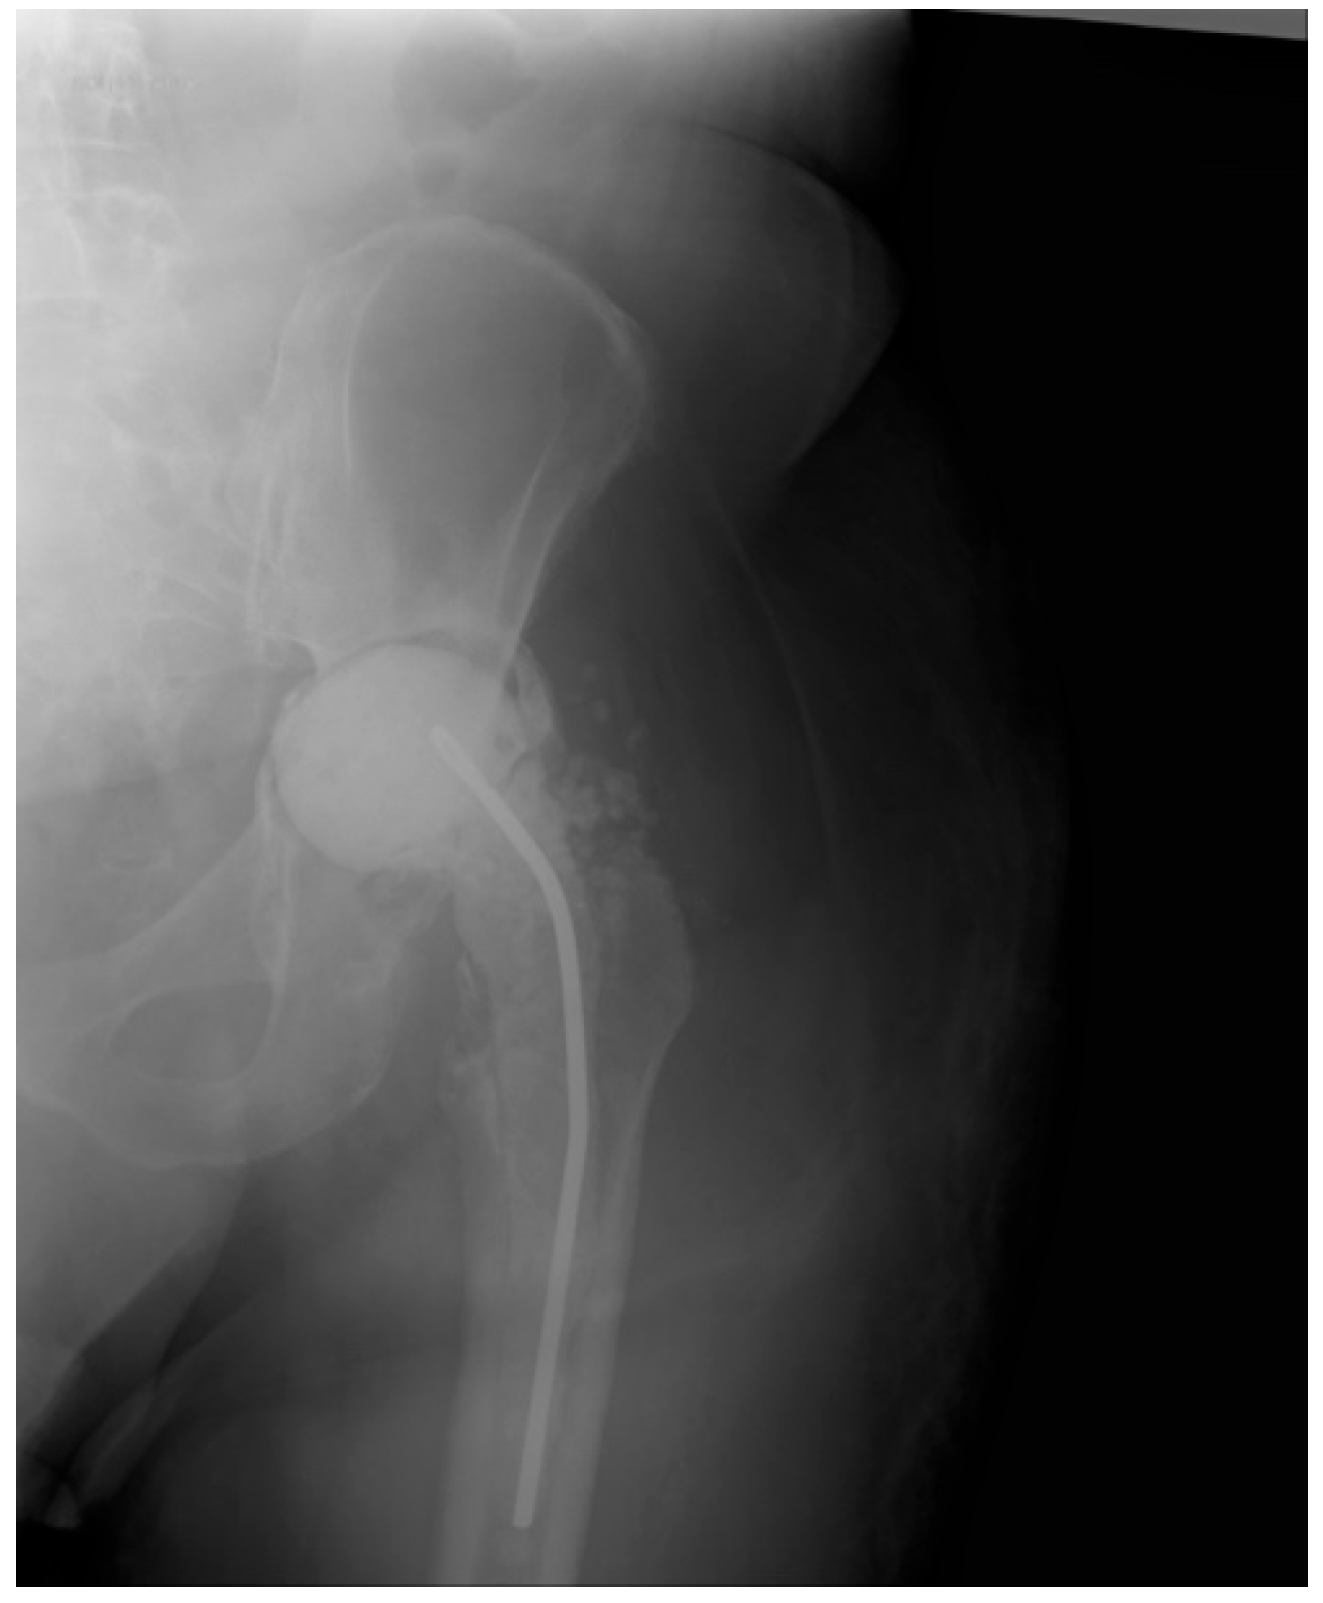

The Efficacy of Antibiotic-Loaded Calcium Sulfate Beads (Stimulan) in Patients with Hip Arthroplasty Infections

2.4. Surgical Procedure